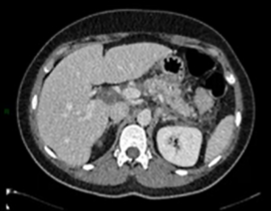

Cas Cliniques - secteur Abdomen

PEZZULLO M. – ULB & MEUNIER P. – ULG